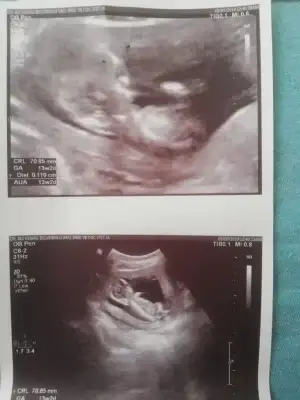

Bizde tahmin alabilir miyiz 13+2

• IMG_20190808_111703.webp

IMG_20190808_111703.webp

31,6 KB · Görüntüleme: 60